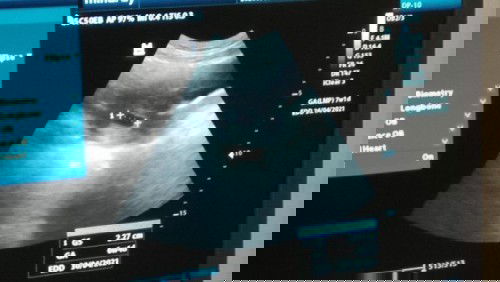

Janin disebelah kanan

Hari ini saya usg bun. Ternyata janin saya nyempil dibagian kanan perut. Apa itu gkpp ya? Yg punya pengalaman seperti saya boleh sharing bun! #hamilpertama_kalinya